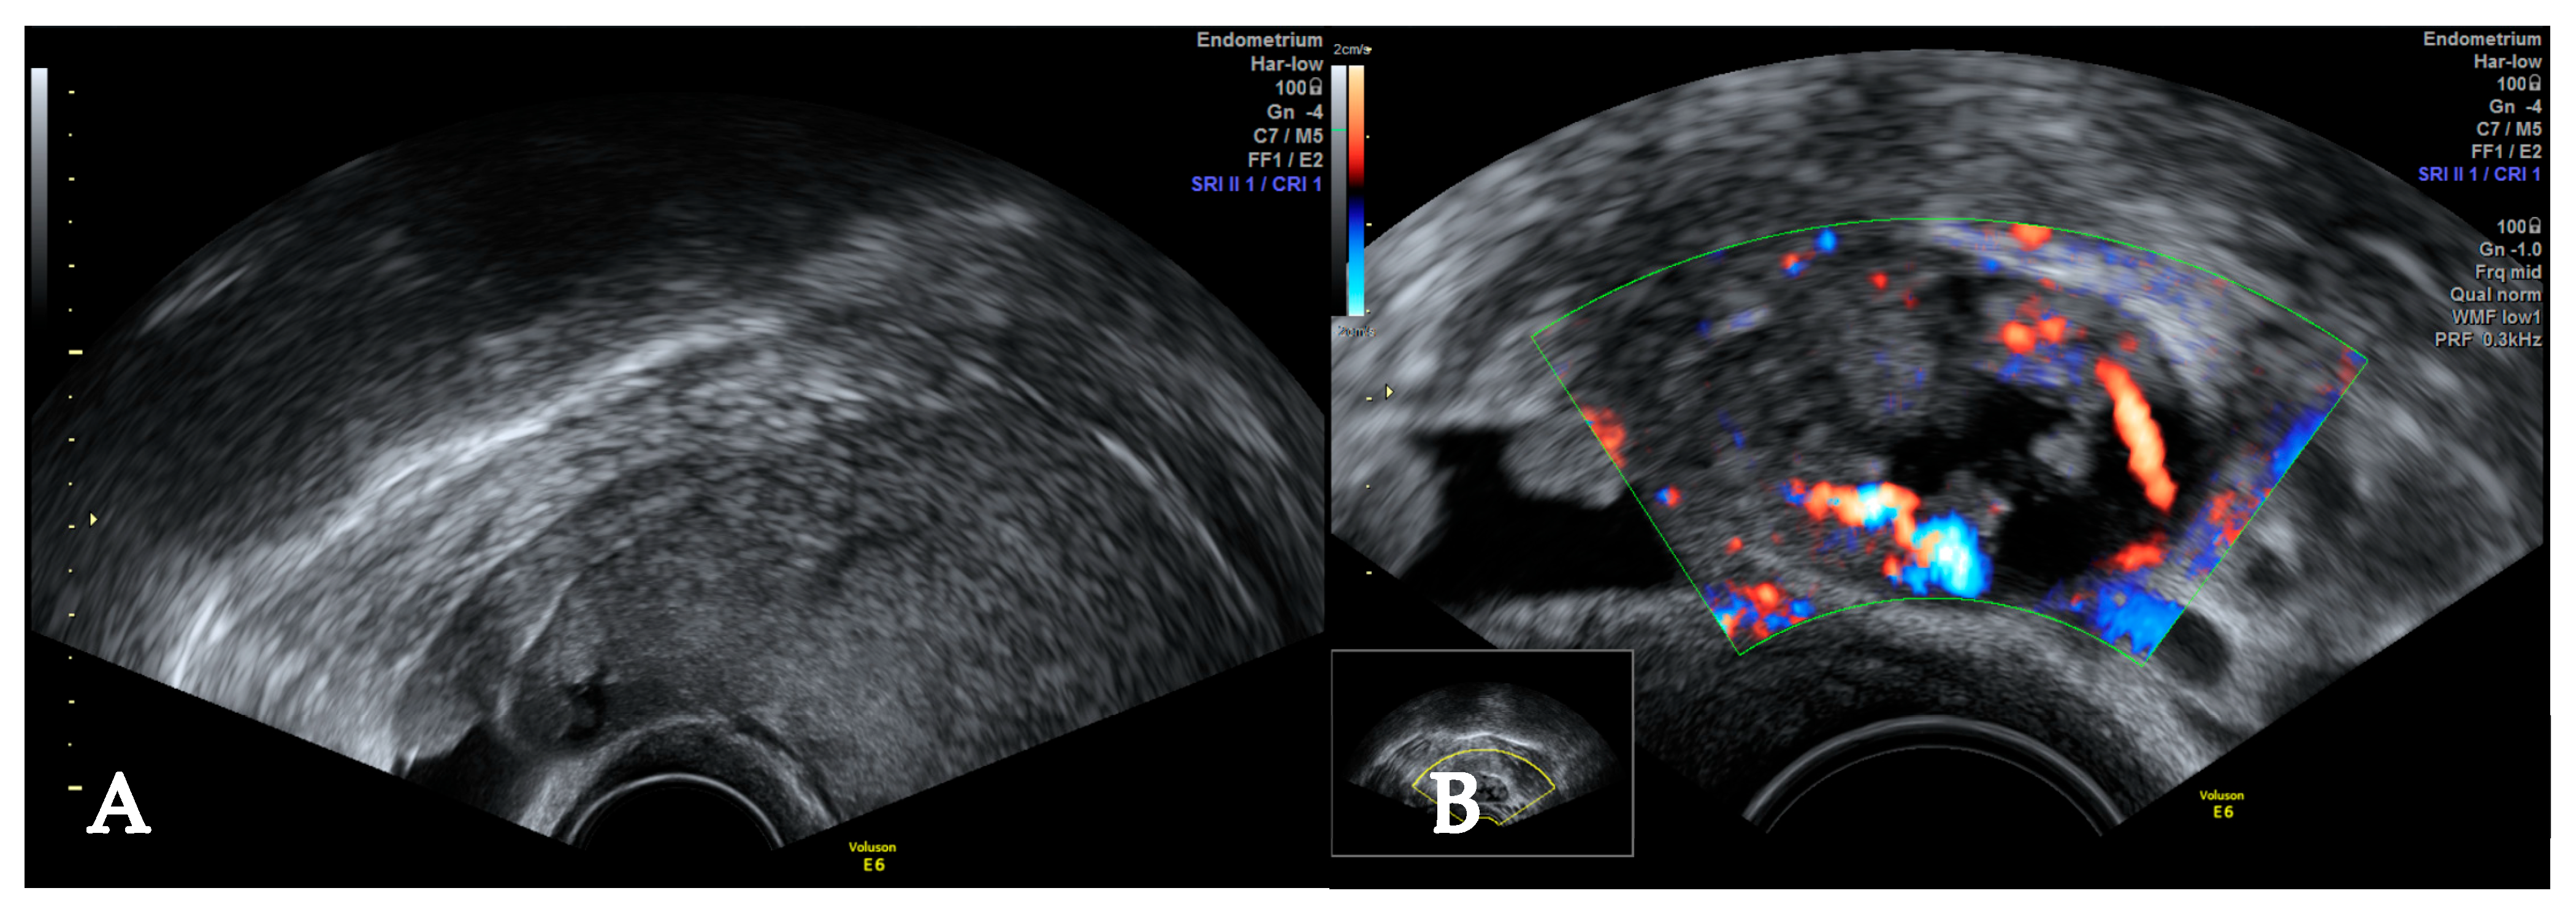

2. Case